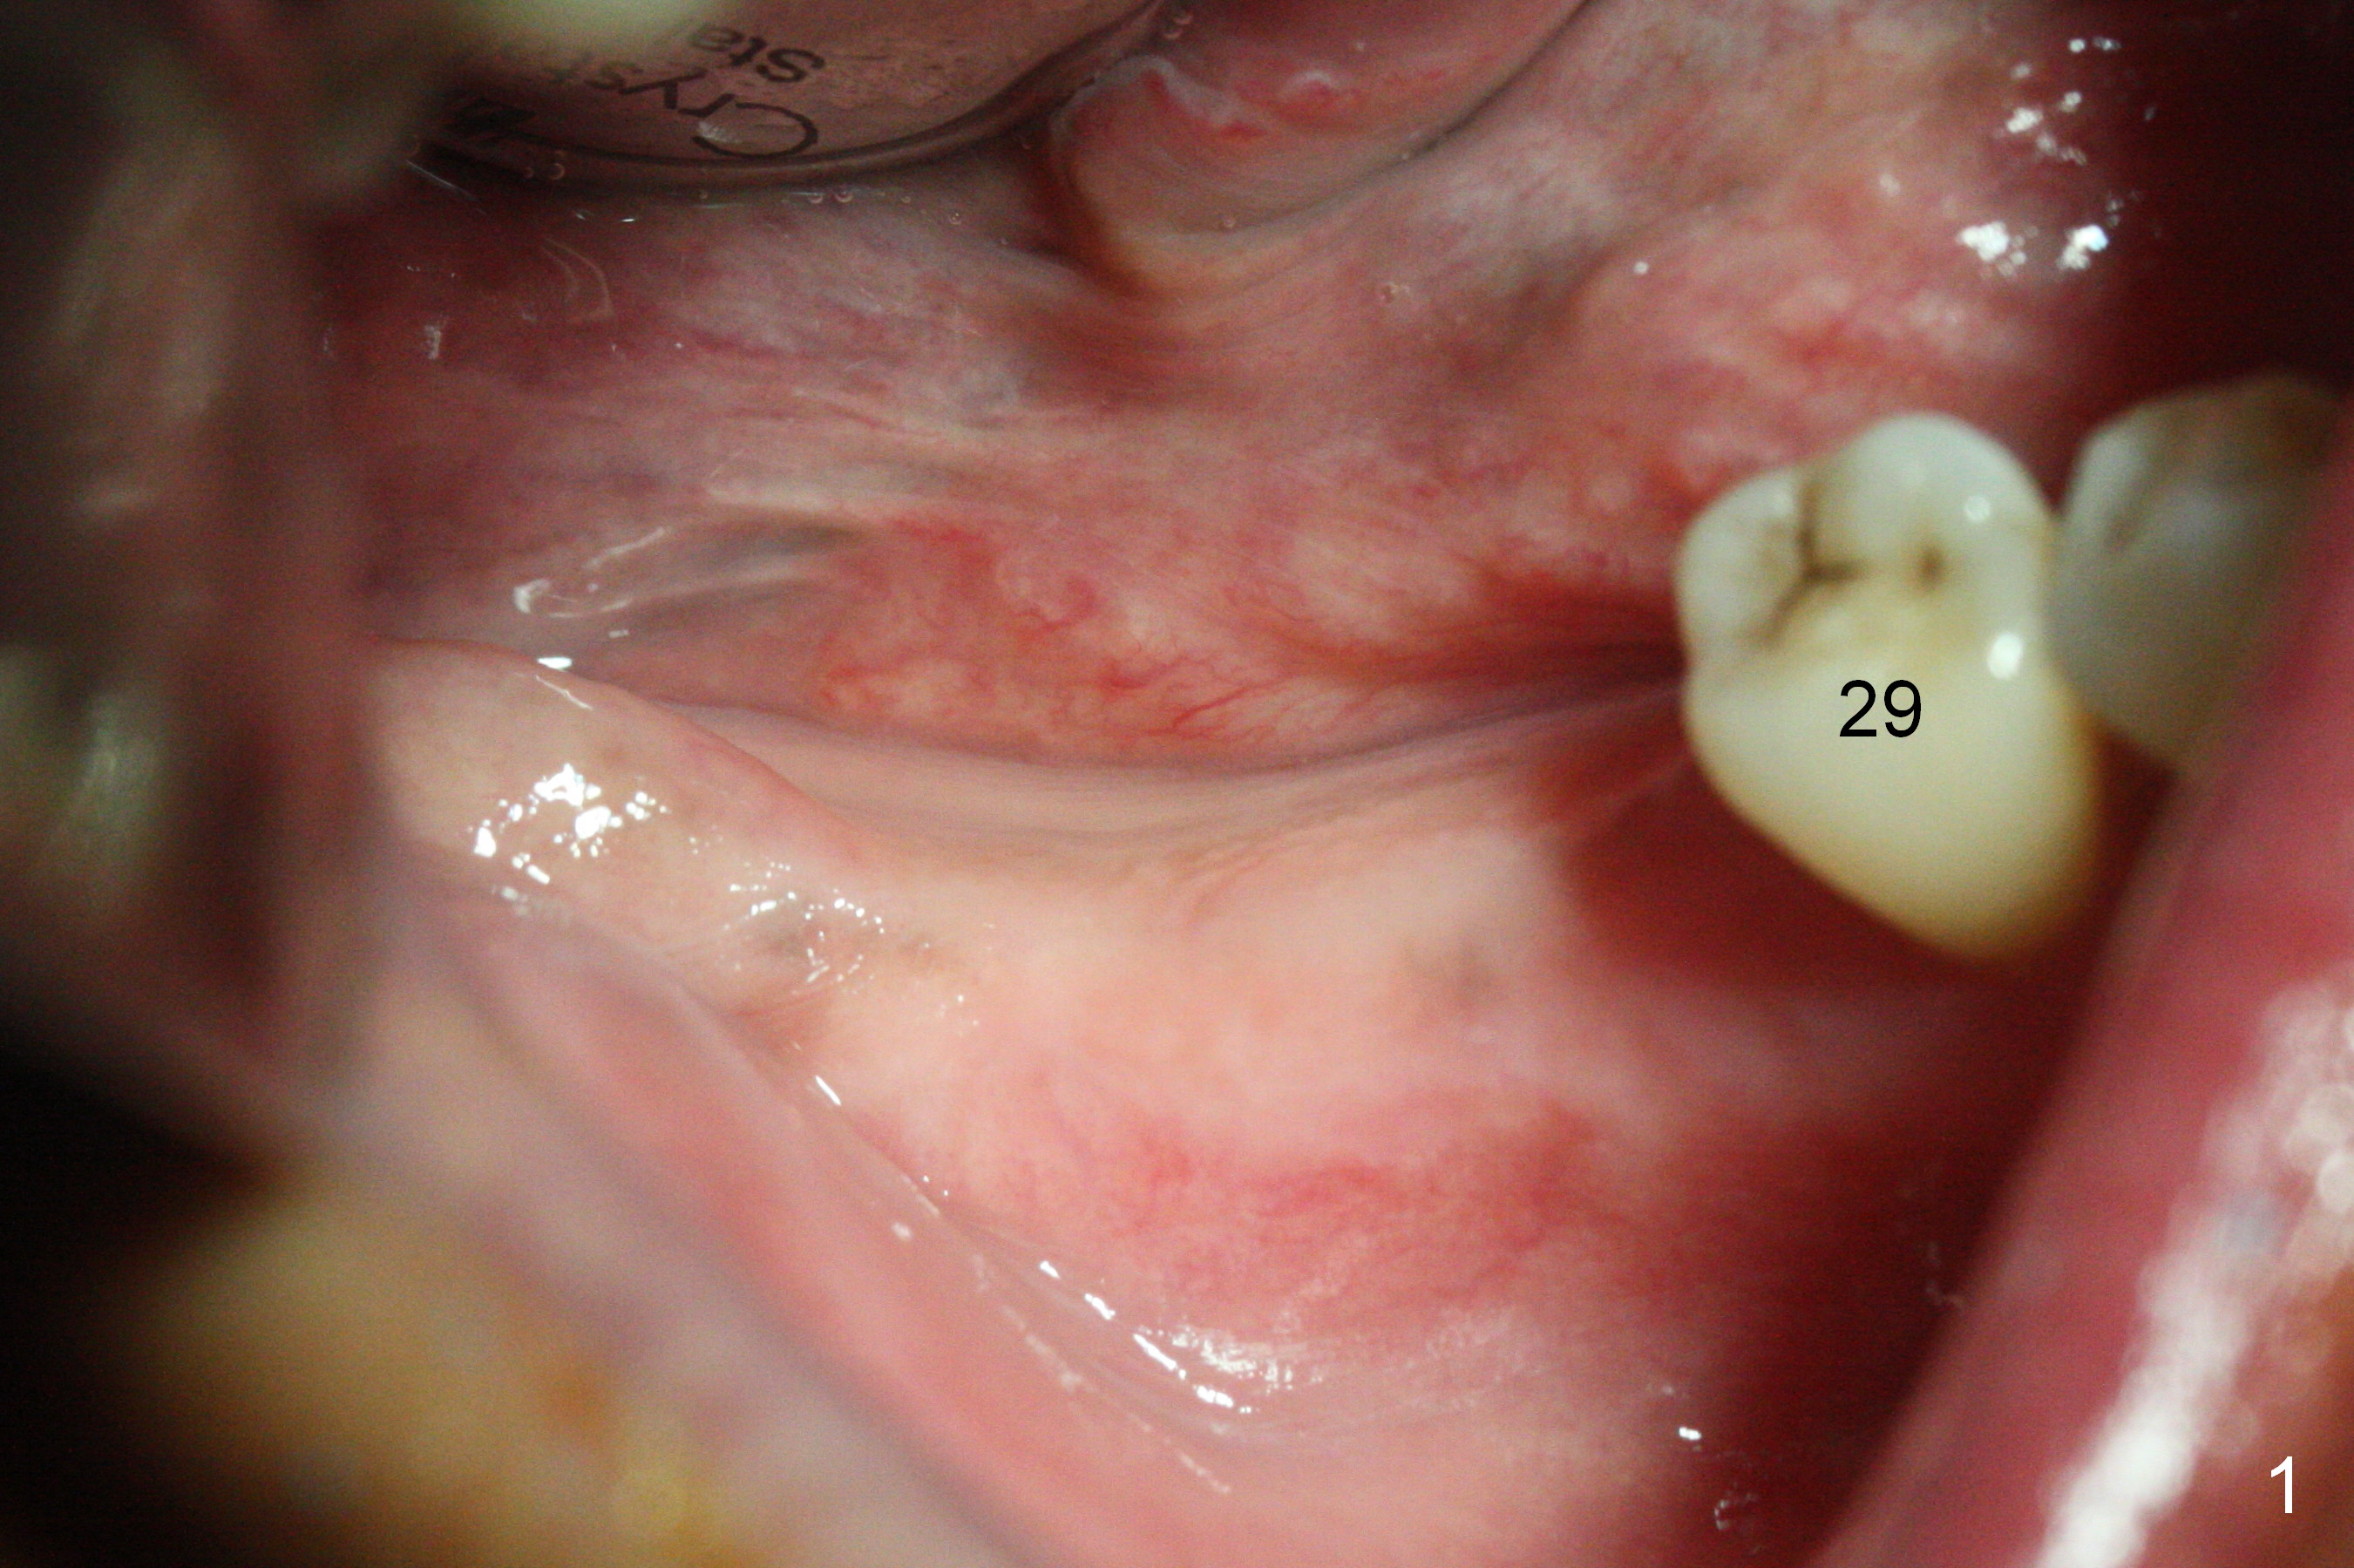

The supraerupted tooth #2 is adjusted using the lower right surgical stent.  Osteotomies are initiated by using starter drill through surgical stent over the ridge (Fig.1) prior to incision.  The initial depths are 10 and 12 mm at the sites of #31 and 30, respectively (Fig.2).  The new sensor with the existing sensor holder cannot reach the deep portion of the lingual vestibule (Fig.2,3).  Without the sensor holder, the #2 sensor with rounded corners has no problem showing the Inferior Alveolar Canal (Fig.4 red dashed line).  The two implants (5x12 and 5x14 mm, Fig.5) are placed with >50 Ncm.  Cemented abutments are immediately placed (6.8x4(2) and 6.8x4(3) mm) to reduce suture tension (after autogenous bone graft and collagen dressing) and hold periodontal dressing in place.  The wound does not heal completely 15 days postop (Fig.6).  The patient reveals that he smokes 1/2 pack per day.  There is crestal bone resorption 4 months postop (Fig.7 *).  It appears that for smokers, implants should be smaller, placed deeper and buried.  In addition, his oral hygiene is not good.